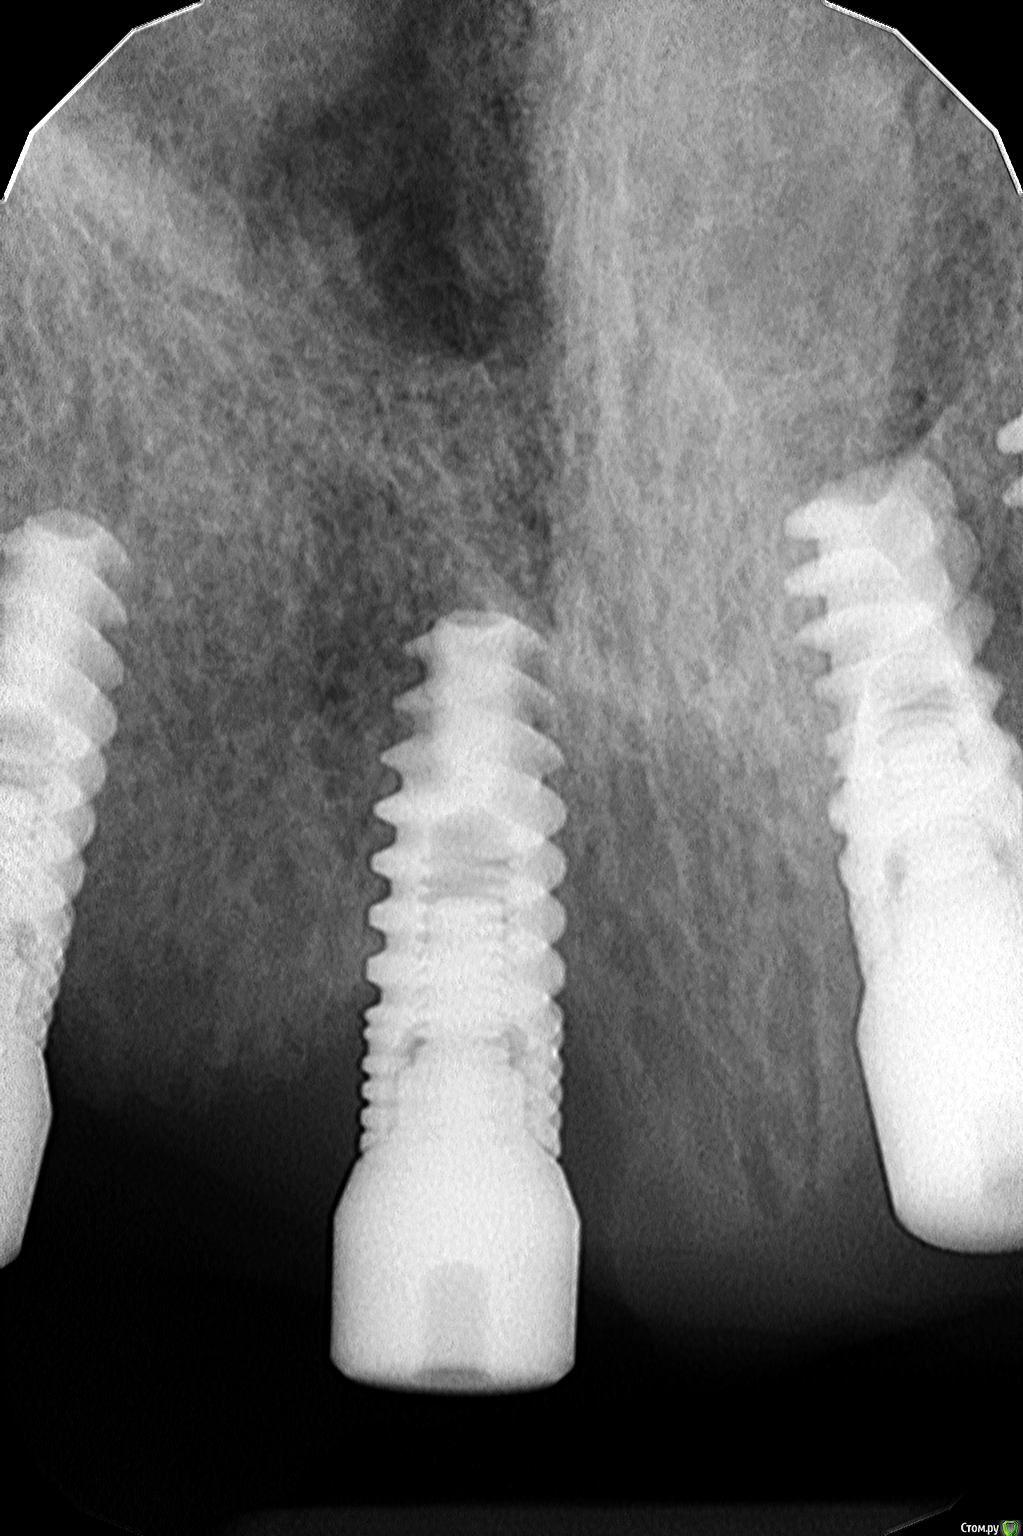

zarbazan Опубликовано 28 марта, 2018 Поделиться Опубликовано 28 марта, 2018 Здравствуйте! Помогите с тактикой лечения периимплантита(опыта нет).Имплантат Альфа-био установлен в позиции 1.1 около 10 мес. назад. 4 месяца стоит формирователь. Есть гиперемия,отёчность, было незначительное гнойное отделяемое. Имплант стабилен. Как будет правильнее дальше действовать? чем можно обработать поверхность импл.,если раскрываться и какие инструменты лучше использовать? ВЗГ снимок прилагаю. Ссылка на комментарий

Dman Опубликовано 29 марта, 2018 Поделиться Опубликовано 29 марта, 2018 Здравствуйте! Помогите с тактикой лечения периимплантита(опыта нет).Имплантат Альфа-био установлен в позиции 1.1 около 10 мес. назад. 4 месяца стоит формирователь. Есть гиперемия,отёчность, было незначительное гнойное отделяемое. Имплант стабилен. Как будет правильнее дальше действовать? чем можно обработать поверхность импл.,если раскрываться и какие инструменты лучше использовать? ВЗГ снимок прилагаю. а еще проще убрать его - я так понимаю рядом много имплантов, справятся без него. Ссылка на комментарий